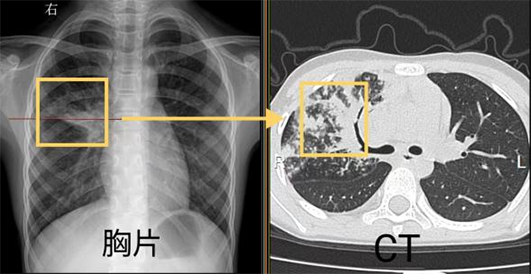

我們先通過同一個病人的胸片和胸部CT對比看一下吧。

左圖胸片黃框中的白色區(qū)域就是肺炎病灶,與右圖CT相同位置表現(xiàn)一致,但CT把病灶顯示的更清晰。

胸片黃框區(qū)域顯示沒有異常,同一位置CT顯示少許肺炎病灶。

對比我們可以發(fā)現(xiàn),胸片可以提供初步的診斷依據(jù),胸部CT能更清晰的顯示病灶形態(tài)及一些微小病灶,比如實變、空洞、支氣管壁的增厚等。因此,在小兒肺炎支原體肺炎的診斷中,胸部CT具有一定的優(yōu)勢。